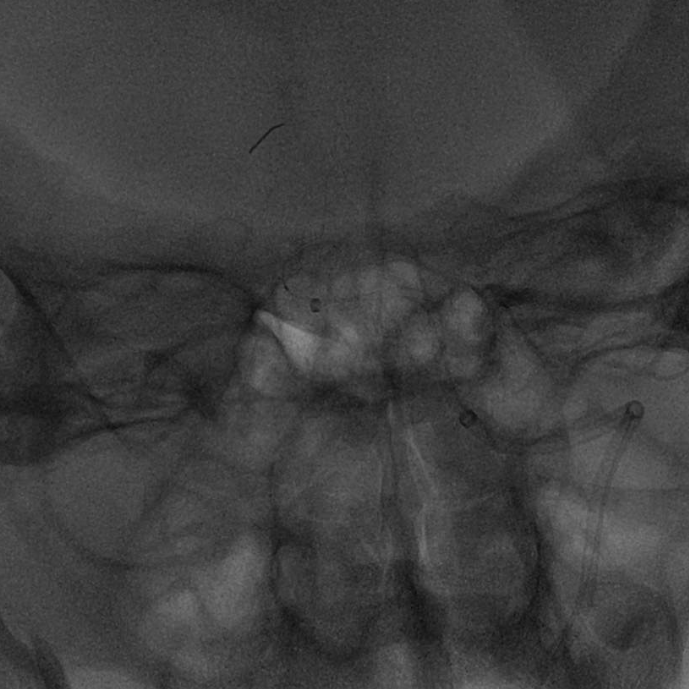

➢头颈部CTA+脑灌注

-

双侧枕叶、丘脑、脑干及双侧小脑半球血流灌注减低,建议MRI检查。

双侧椎动脉V4管腔闭塞,建议DSA检查。

双侧颈内动脉虹吸段钙化斑块,管腔中-重度狭窄;双侧大脑中动脉M1段、大脑后动脉硬化,管腔轻微-轻度狭窄。

双侧大脑前动脉共干。

患者为老年男性,病情进展加重快,入院时已超静脉溶栓时间窗,意识障碍逐渐加深,NIHSS评分:13分;头颅CT未见明显梗死病灶;头颈部CTA+脑灌注提示:双侧枕叶、丘脑、脑干及双侧小脑半球血流灌注减低,双侧椎动脉V4管腔闭塞。

主动脉弓造影提示双侧椎动脉V4段闭塞。

左侧椎动脉造影提示椎动脉V4段闭塞。